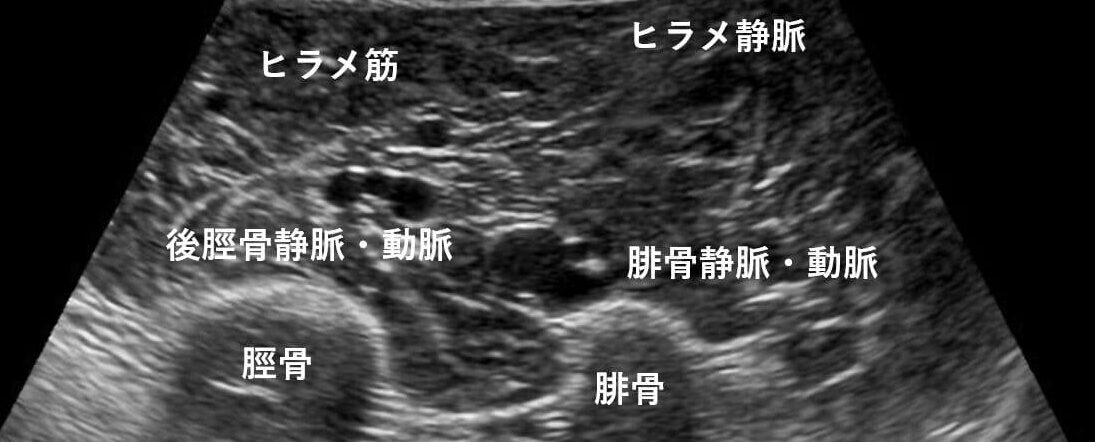

特に【後脛骨静脈】と【腓骨静脈】でしょうか。

なので、側を走行している血管はそれぞれ後脛骨静脈(前脛骨はふくらはぎからではなく下腿前面からスキャンすれば描出できます)、腓骨静脈と考えられます。

個人的には、ヒラメ筋内側にに沿って走行する血管は後脛骨静脈であることが多いのかなと。

後脛骨動脈と静脈は並走しているので(動脈を挟んで静脈が2本走行している)TIMSに隣接している静脈・動脈→後脛骨静脈・動脈として認識出来るのではないかと思います。

個人的には、脛骨とヒラメ筋の間を滑るように走行している血管のイメージです。